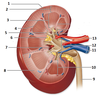

- Fibrous capsule

- Renal cortex

- Renal Medulla

- Corticomedullary junction

- Renal papilla

- Adipose tissue in renal sinus

- Renal sinus

- Renal lobe

- Ureter

- Renal pyramid

- Renal vein

- Renal pelvis

- Renal artery

Cp – capsule

C – renal cortex

M – renal medulla

P – renal papilla

U – ureter